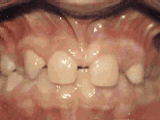

第八种

牙列稀疏,牙槽骨过长,或者牙齿少,光头强就是这类。导致排列太宽松,零零散散,经过矫正后的是这样的